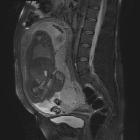

MRI

MRI is the gold standard imaging modality for the placenta and its relationship to the cervix, although in most instances it is not required. Sagittal images best demonstrate the relationship of the placenta to the internal cervical os.